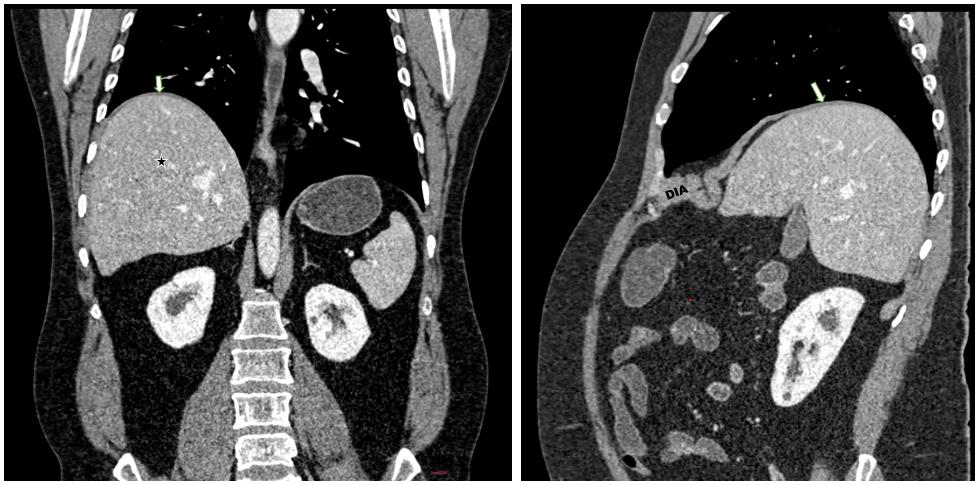

position [Figure 1] There was moderate to marked elevation of the

posterior aspect of the right hemidiaphragm along with upward

displacement of the right hepatic lobe, suggesting diaphragmatic

eventration [Figure 2]. Additionally, a right-sided partial duplex

Figure 2: Coronal and sagittal sections demonstrating marked elevation

of the posterior right hemidiaphragm (white arrow). The anterior right

hemidiaphragm appears thickened, while the posterior dome is markedly

thinned, with upward displacement of the right lobe of liver (★), consistent

with diaphragmatic eventration.